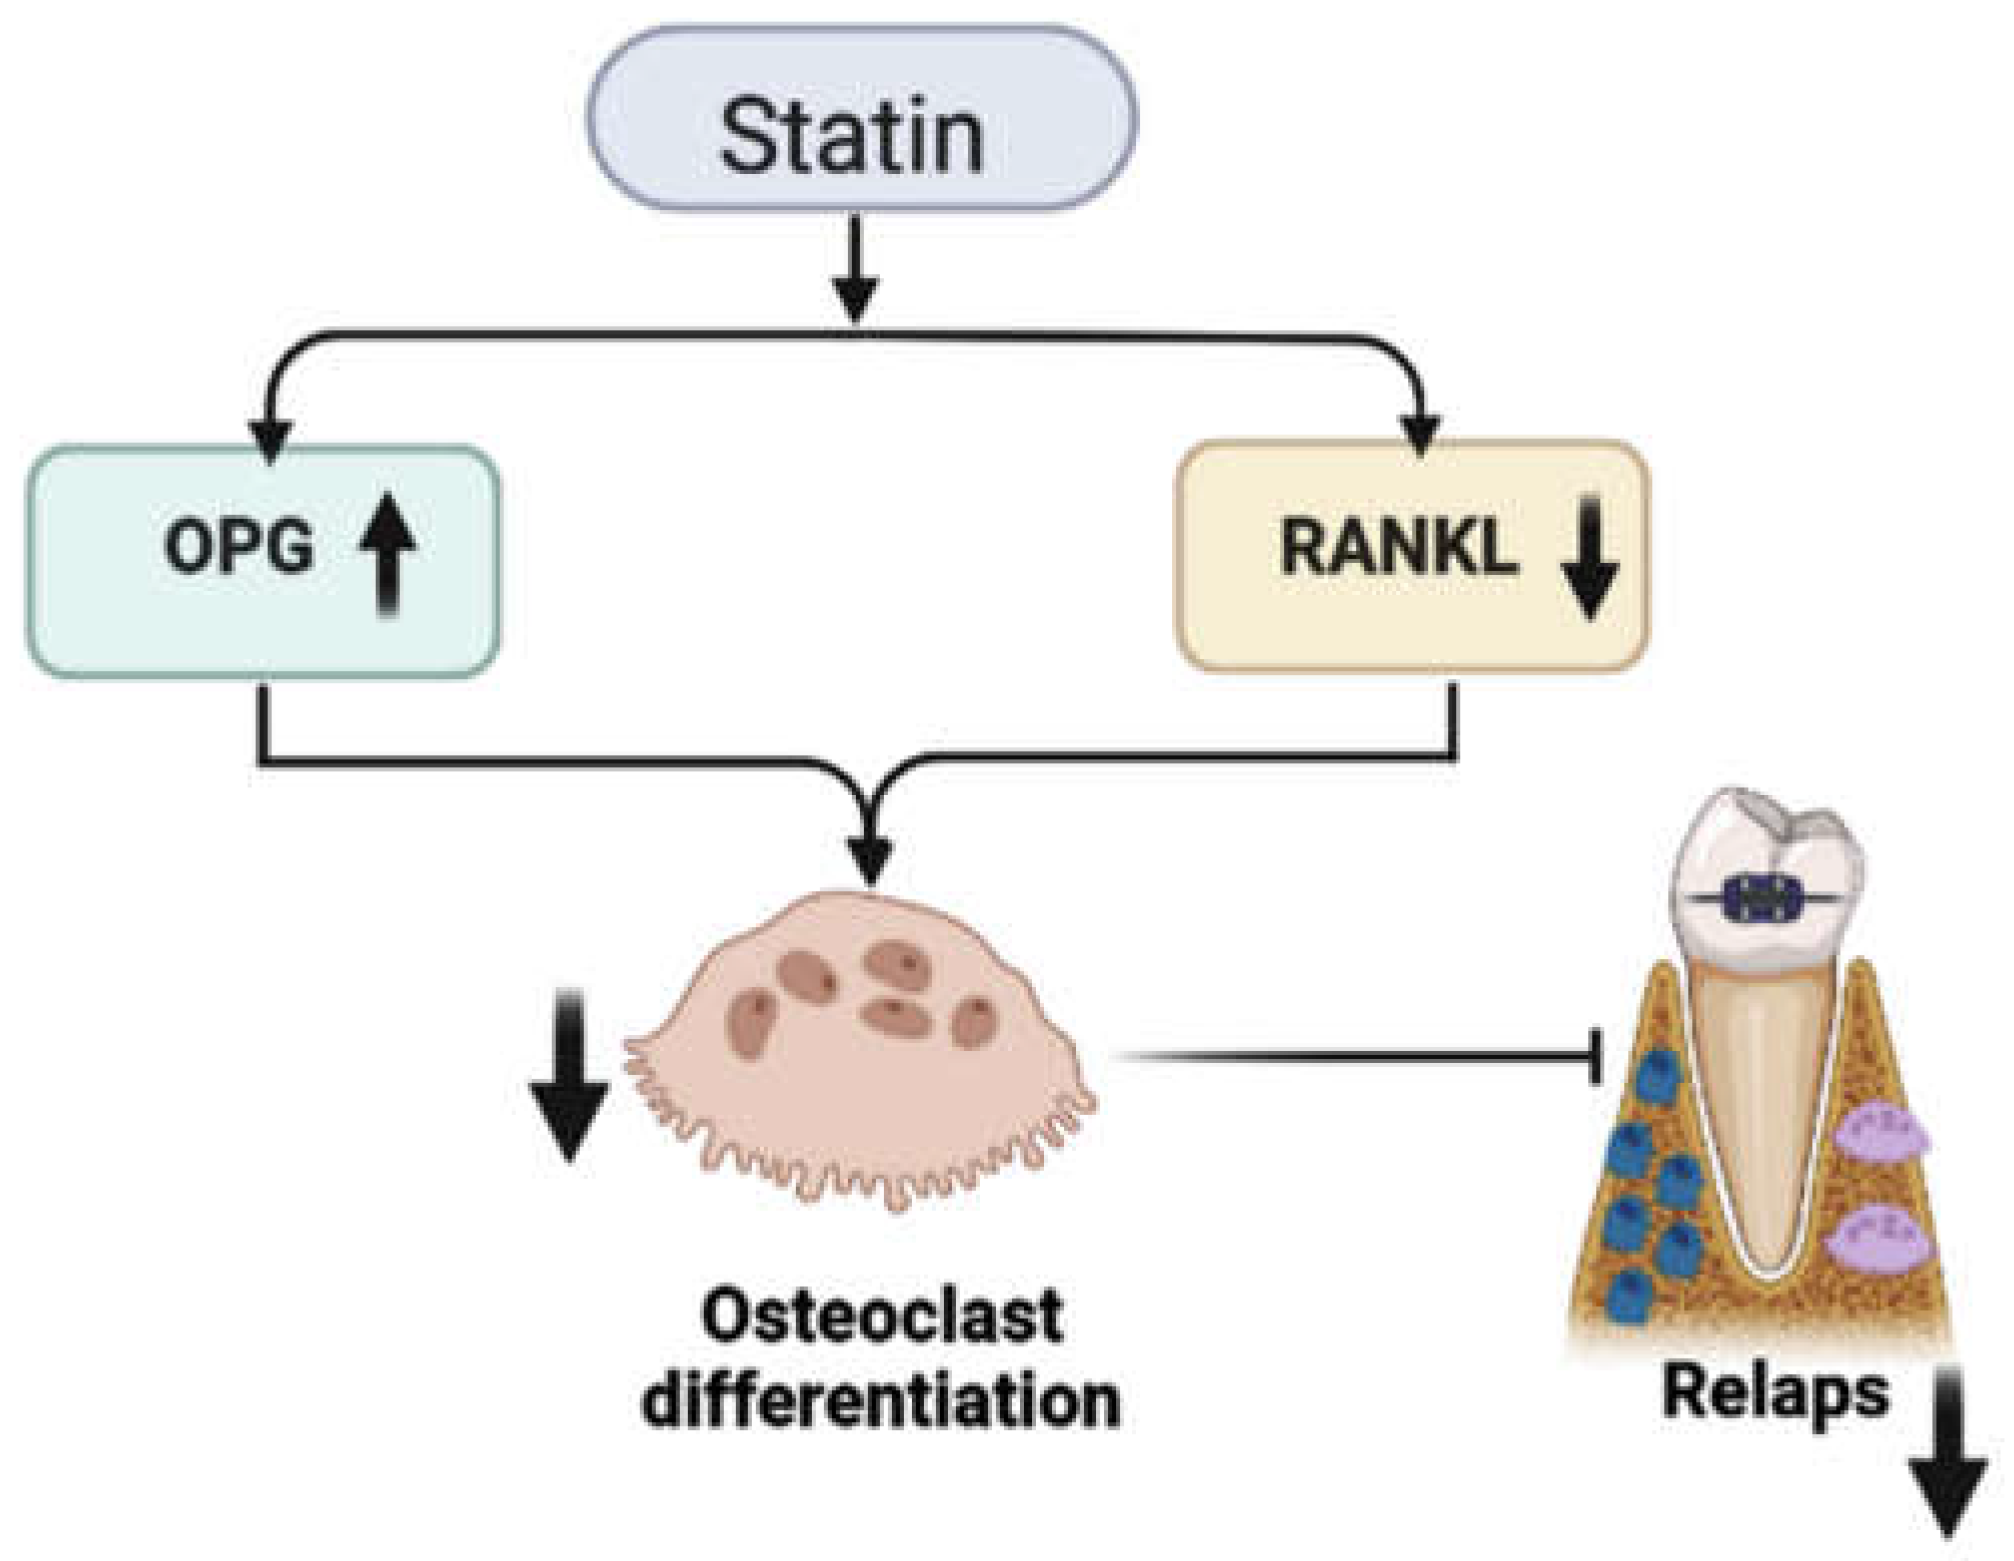

3. Statins’ Inhibitory Effect on Relapse after Orthodontic Treatment

- Boyce, B.F.; Xing, L. Functions of RANKL/RANK/OPG in bone modeling and remodeling. Arch. Biochem. Biophys. 2008, 473, 139–146. [Google Scholar] [CrossRef] [PubMed] [Green Version]

- Ruan, F.; Zheng, Q.; Wang, J. Mechanisms of bone anabolism regulated by statins. Biosci. Rep. 2012, 32, 511–519. [Google Scholar] [CrossRef] [PubMed] [Green Version]

- Zhang, Y.; Bradley, A.D.; Wang, D.; Reinhardt, R.A. Statins, bone metabolism and treatment of bone catabolic diseases. Pharmacol. Res. 2014, 88, 53–61. [Google Scholar] [CrossRef]

- Han, G.; Chen, Y.; Hou, J.; Liu, C.; Chen, C.; Zhuang, J.; Meng, W. Effects of simvastatin on relapse and remodeling of periodontal tissues after tooth movement in rats. Am. J. Orthod. Dentofac. Orthop. 2010, 138, 550.e1–550.e7. [Google Scholar] [CrossRef]

- Viereck, V.; Gründker, C.; Blaschke, S.; Frosch, K.H.; Schoppet, M.; Emons, G.; Hofbauer, L.C. Atorvastatin stimulates the production of osteoprotegerin by human osteoblasts. J. Cell Biochem. 2005, 96, 1244–1253. [Google Scholar] [CrossRef]

- Dolci, G.S.; Portela, L.V.; Onofre de Souza, D.; Medeiros Fossati, A.C. Atorvastatin-induced osteoclast inhibition reduces orthodontic relapse. Am. J. Orthod. Dentofac. Orthop. 2017, 151, 528–538. [Google Scholar] [CrossRef] [PubMed]

| Dolci et al. [62] | ATO systemic administration, 15 mg/kg | Statins reduce orthodontic relapse in rats by modulating bone remodeling. Decreased osteoclastogenesis and increased OPG protein expression explain this effect. |